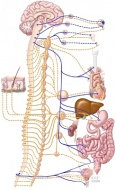

Симпатиковата нервна система се състои от нерви, които са разположени в гръдната и лумбалната област...